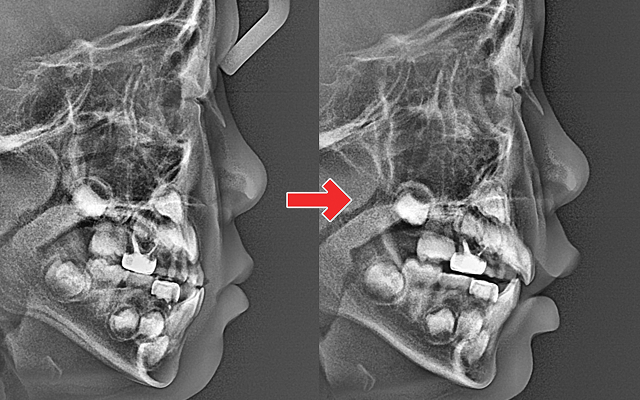

턱 성장 방향과 교합을 조기에 바로잡아

평생 바른 치열과 얼굴 균형을 만듭니다.

교정 중 성장 모니터링으로

얼굴 균형까지 함께 관리